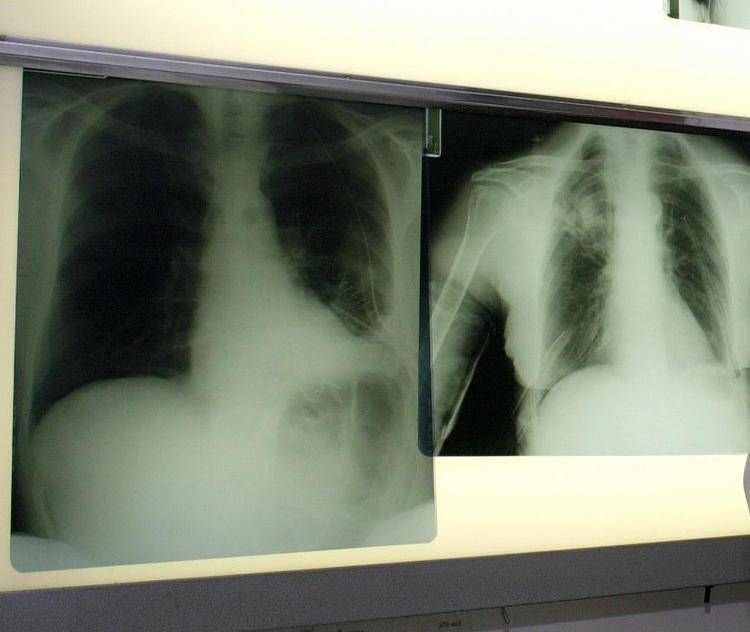

La triplice terapia con budesonide/glicopirronio/formoterolo fumarato (Bgf), già autorizzata per il trattamento della broncopneumopatia cronica ostruttiva (Bpco) negli adulti, ha ricevuto parere positivo dal Comitato per i medicinali per uso umano (Chmp) dell'Agenzia europea per i medicinali (Ema) per l'utilizzo nell'Unione europea di un propellente innovativo di nuova generazione con un potenziale di riscaldamento globale (Gwp) prossimo allo zero. La triplice terapia con budesonide/glicopirronio/formoterolo fumarato è il primo farmaco somministrato tramite inalatore predosato pressurizzato (pMdi) a utilizzare un propellente green, con un potenziale di riscaldamento globale inferiore del 99,9% rispetto ai propellenti attualmente utilizzati nei farmaci inalatori. Questa triplice terapia a combinazione fissa avrà ora un impatto ambientale in termini di emissioni di carbonio comparabile a quella dei farmaci inalatori che non necessitano di propellente.

Le malattie respiratorie croniche, tra cui la Bpco e l'asma ricorda AstraZeneca colpiscono centinaia di milioni di persone a livello globale. I farmaci inalatori respiratori somministrati tramite pMdi rappresentano il 76% dell'utilizzo di inalatori a livello globale e contribuiscono per lo 0,04% alle emissioni globali di gas serra. Gli studi dimostrano che il maggiore impatto ambientale associato alle malattie respiratorie deriva dal mancato controllo della patologia e dal conseguente aumento della necessità di ricorrere a servizi sanitari. L'implementazione di linee guida basate sulla generazione di evidenze nella pratica clinica può contribuire a ridurre le riacutizzazioni e i ricoveri ospedalieri, migliorare gli outcome per i pazienti e anche diminuire l'impatto delle emissioni di carbonio complessive associate alle cure respiratorie.